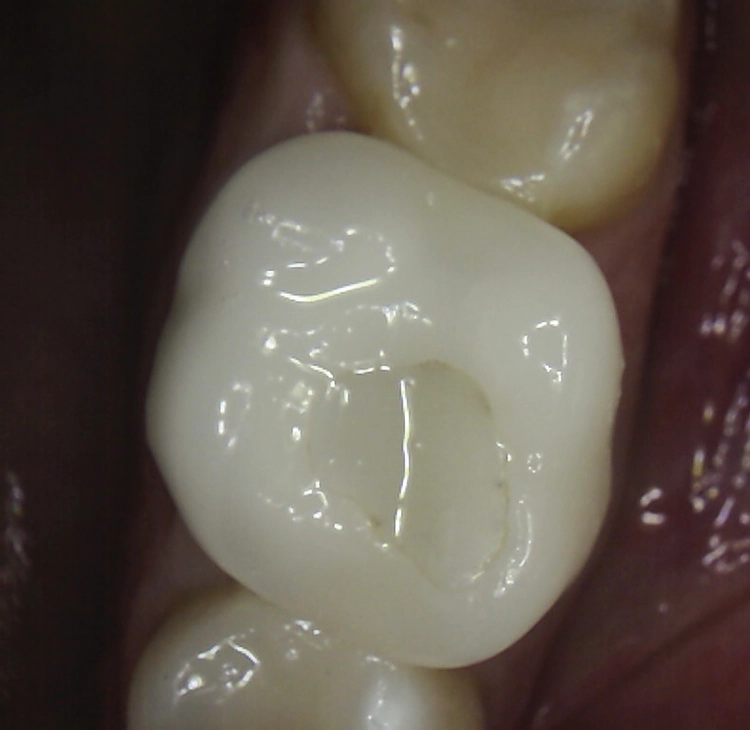

Abb. 2: Repräsentativer Fall von ABH Grad B Septus Typ II. a) Ansichten vor der Installation. Röntgenaufnahme der periapikalen Läsion an einem wurzelkanalbehandelten Molaren und klinische Ansicht der Typ-II-Socket nach der Extraktion. b) Die Ansichten nach der Installation zeigen das Implantat innerhalb des interradikulären Septums und das über dem Implantat platzierte A-PRF. c) Nachuntersuchungen nach 10 Tagen bzw. 2,1 Monaten. Die Röntgenaufnahme zeigt die Knochenbildung zwischen der Sinusmembran und dem apikalen Teil des Implantats. d) Jüngste Nachuntersuchung nach Einsetzen der Prothese.

Abb. 3: Repräsentativer Fall von Grad A Typ I. a) Präoperative Ansicht. Röntgenbild der periapikalen Läsion an einem wurzelkanalbehandelten Molaren. Die Höhe des Alveolarknochens zeigt Grad A an. b) Klinische und radiographische Ansicht der Implantatinsertion unter Verwendung einer Einheilscheibe mit großem Durchmesser (6×8 mm). A-PRF wurde um das Implantat und unter der Scheibe platziert. c) Nachuntersuchung nach 5,9 Monaten vor und nach der Zementierung und Aufbereitung. d) Jüngste Nachuntersuchung nach Einsetzen der Prothese

Die SDS-Zirkoniumdioxidimplantate wurden mit zementierten Pfosten weiter aufbereitet (Abb. 1d, 3 und 4c) und nach 4,74 + 0,95 Monaten Einheilzeit mit endgültigen Kronen versorgt. Die Balkonform ermöglichte ein natürliches Emergenzprofil, das die definitiven Kronen wie die Standardform ausrichtete sowie die Gesundheit des Weichgewebes und die Osseointegration förderte. Bei jeder Nachuntersuchung wurden Stabilität des Implantats, Zustand des umgebenden Gewebes und Vorhandensein von Zahnstein beurteilt.